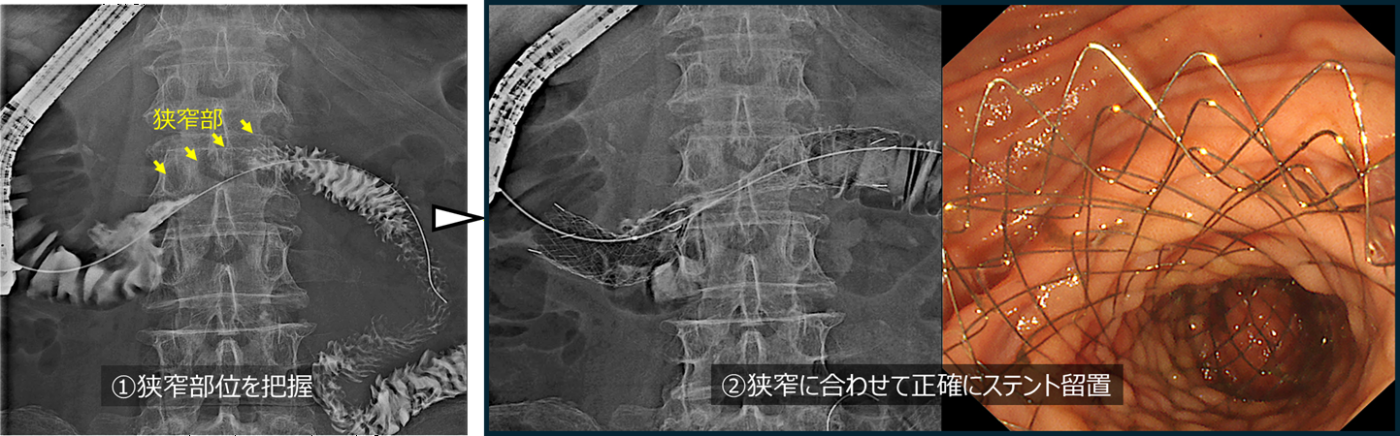

膵癌による胆道狭窄に対して胆道ドレナージを行った症例

膵癌に対して化学療法中でした。腫瘍によって、胆汁の流れ道である胆道が狭窄し、黄疸を発症し化学療法の中止を余儀なくされました。そのため、ERCPでの胆道ドレナージを行う方針としました。

まず内視鏡を十二指腸まで進め、胆管と膵管が合流する十二指腸乳頭(主乳頭)を確認します。専用のカテーテルを用いて胆管を選択し、ガイドワイヤーを胆管内へ挿入します。必要に応じて内視鏡的乳頭切開術を行い、胆管への処置を行いやすくします。これらの操作は透視装置(X線)で位置を確認しながら安全に進めます。

透視画像で胆道の狭窄を確認します。狭窄部は胆管の下流側にあり、この部位は遠位胆管と呼ばれます。この遠位胆管の狭窄部にステントを留置することで、胆汁の流れを改善します。本症例では金属ステントを1本留置し、胆汁の流れを確保しました。

本症例では高度の黄疸を認めていましたが、速やかに胆道ドレナージを行うことで黄疸は改善し、その後化学療法を再開することができました。